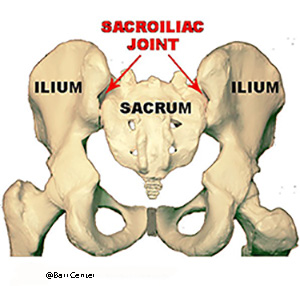

The large, C-shaped sacroiliac (SI) joint connects the pelvic bones (the ilia) to the sacrum at the base of the spine. There are a pair of SI joints, one on either side of the tailbone. Serving as shock absorbers for the pelvis and low back, the SI joints move constantly when the body is in motion, helping to provide stability and structural support to the lower part of the body.

The most common cause of Sacroiliac Joint Dysfunction is from traumatic injury, whether from a fall or traffic accident or from repetitive rotation of the lumbar spine and pelvis during sports and work-related activities. Inflammation of the sacroiliac joints is very common and often occurs for no apparent reason. Mechanical dysfunction of the SI joints is also quite common and we routinely assess for mechanical dysfunction in the office and perform osteopathic manipulation which can be quite helpful. Over stretching, straining, and tearing of the SI joint support ligaments then cause weakening and abnormal motion of the joint, resulting in painful ligaments and joints as well as spasm. Postural imbalances as well as leg length inequalities can also cause Sacroiliac Joint Dysfunction. As a result of this, there can be a

The most common cause of Sacroiliac Joint Dysfunction is from traumatic injury, whether from a fall or traffic accident or from repetitive rotation of the lumbar spine and pelvis during sports and work-related activities. Inflammation of the sacroiliac joints is very common and often occurs for no apparent reason. Mechanical dysfunction of the SI joints is also quite common and we routinely assess for mechanical dysfunction in the office and perform osteopathic manipulation which can be quite helpful. Over stretching, straining, and tearing of the SI joint support ligaments then cause weakening and abnormal motion of the joint, resulting in painful ligaments and joints as well as spasm. Postural imbalances as well as leg length inequalities can also cause Sacroiliac Joint Dysfunction. As a result of this, there can be a  disruption of movement in the joint (either too much or too little).

disruption of movement in the joint (either too much or too little).

A sacroiliac injection places a pain-numbing medicine and steroid directly into the sacroiliac (SI) joint. There are two sacroiliac joints, one located on either side of the sacrum (see arrow pointing to the left sacroiliac joint). The benefit of this procedure is to reduce inflammation, help confirm the SI joint as the source of pain, and better allow a physical therapist to treat the joint.